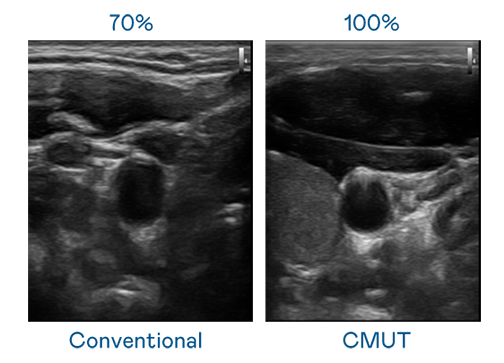

CMUT 技术是一种用电容式微机电元件来产生超音波讯号的技术。与传统 PZT 压电式技术相比,CMUT 频宽增加 30%,更宽频的超音波讯号让影像解析度大幅提升,是实现高影像品质医疗超音波扫描、促进精准医疗发展的关键技术。

超音波影像的解析度高低,首先取决于探头能发出的讯号频宽。星空电子 CMUT 可提供高清晰的超音波讯号,提供高频宽、高灵敏度、影像纹理细节更高的超音波影像,协助医护人员缩短影像判读时间及利用精准的医疗影像进行诊断。